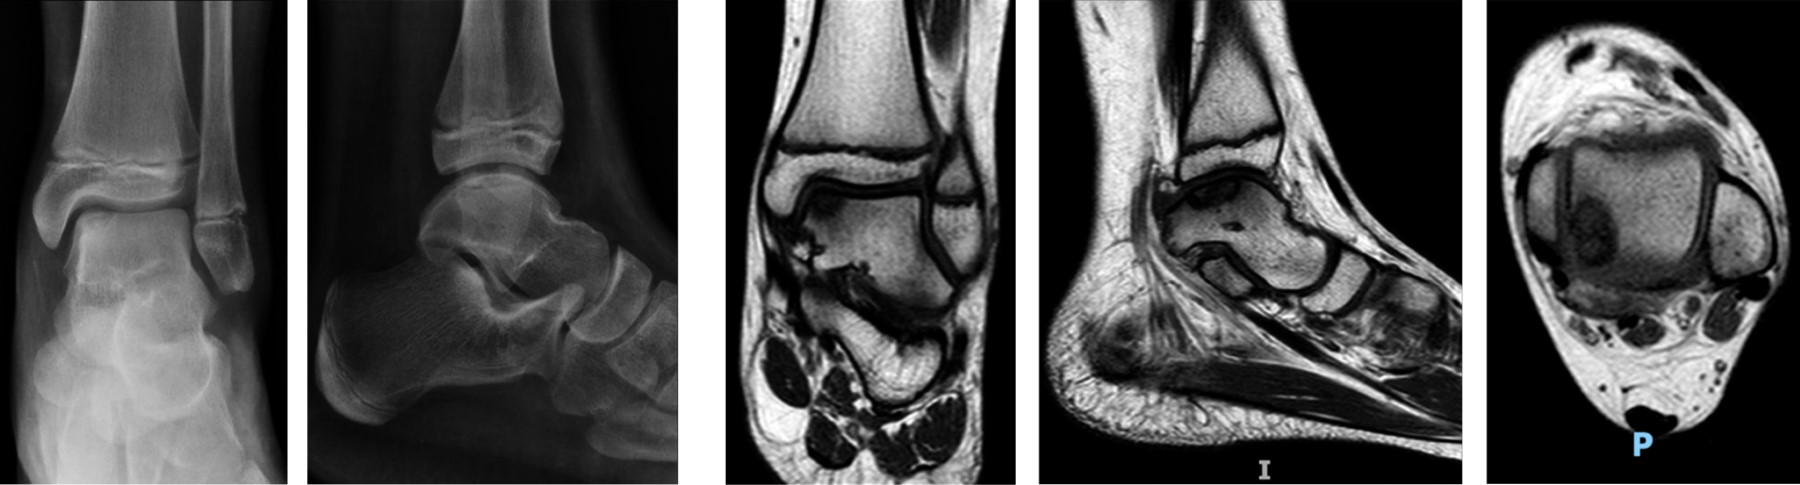

Figura 4